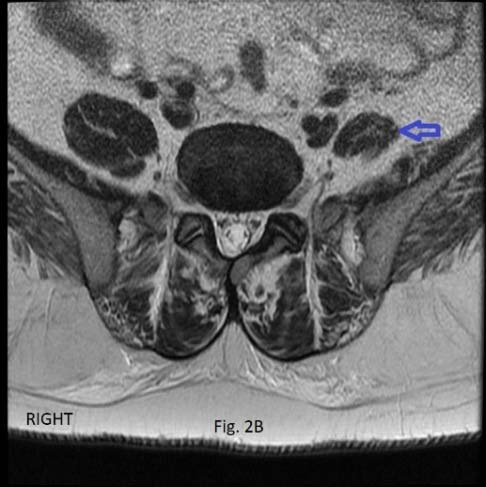

The analytic process was three-fold: a) search for disc herniation in the three lower lumbar discs, with emphasis of its location central or lateral, 2) assess the attachment of the PM muscle to both sides of the disc, and verify if the attachment was present, partial, or absent (nonattachment), and 3) verify whether there was disc herniation and partial or absent attachment of the PM muscle to the same disc. To facilitate the assessment of the PM muscle adherence to the disc's borders, and to correctly locate the herniated disc, the disc's surface was divided into four quadrants of equal size. The four quadrants were obtained by drawing two perpendicular lines at the center of the disc (Figure 1). The quadrants were named: right anterolateral, left anterolateral, right posterior, and left posterior. When the muscle fascicles adhered to the disc in all four quadrants, it was considered as complete attachment (Figure 1). The lack of contact of the PM muscle fascicles with the disc border in one, or two, or three quadrants was defined as partial attachment (Figure 2a). The lack of contact of the PM muscle fascicles to the disc in all four quadrants was defined as total absence of attachment or nonattachment (Figure 2b).

At the L5-S1 disc level, none of the 175 patients presented with a complete PM attachment to the disc. However, 16 (9.1%) patients presented with a partial attachment of the PM muscle to the disc; while 159 (90.8%) patients had nonattachment of the PM muscle to the disc.

Amongst the 16 patients with PM partial attachment to the disc, 75.0% had disc herniation. From the 159 patients with nonattachment of the PM muscle, 60% suffered from disc herniation (Figure 3). Statistically, the difference in the prevalence of disc herniation in patients with partial attachment and those with nonattachment was insignificant, p=0.371.